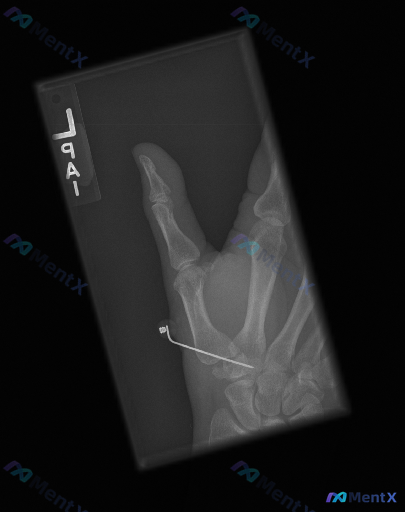

整理到一份左腕术后的复查影像资料,想和大家讨论一下当前的优先级判断方向。 基本背景:左腕创伤术后,本次复查左手腕正位X光片。 影像所见: 1. 内固定物:舟骨腰部可见一枚金属螺钉,位置大致沿舟骨长轴;第一掌骨基底部与大多角骨附近可见两枚交叉克氏针,针尾部延伸至软组织外/影像边缘。 2. 骨折与骨骼:...

整理到一份左侧腕关节正位X线的影像资料,情况如下: - 患者有腕骨骨折手术史 - 影像显示舟骨与月骨区域有交叉克氏针内固定,针尾位于桡侧软组织内 - 舟骨及相关腕骨的骨皮质轮廓尚完整,因金属伪影遮挡,隐匿性骨折线排查受限 - 桡侧皮下及近端软组织内可见散在多个小点状高密度影 - 腕骨间排列尚可,桡腕...